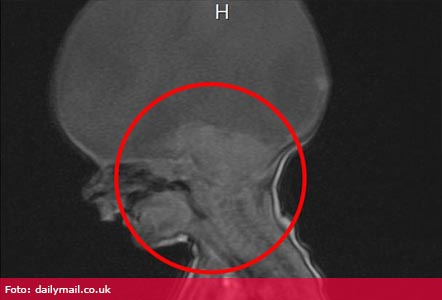

Aaron Murray, băieţelul care s-a născut în urmă cu doi ani cu boala Holoprosencephaly (HPE), a uimit pe toată lumea, inclusiv medicii, după ce a rostit primul cuvânt. Aaron a fost diagnosticat cu această boală rară chiar la naştere. Creierul unui astfel de copil nu este unul complet, chiar dacă o astfel de persoană se poate mişca singură şi poate respira. Medicii i-au spus Emmei, mamei sale în vârstă de 24 de ani, că în câteva minute copilul poate muri şi astfel totul a fost urgentat pentru a-i putea face micuţului botezul în maternitate. Aaron s-a născut cu doar un trunchi cerebral.